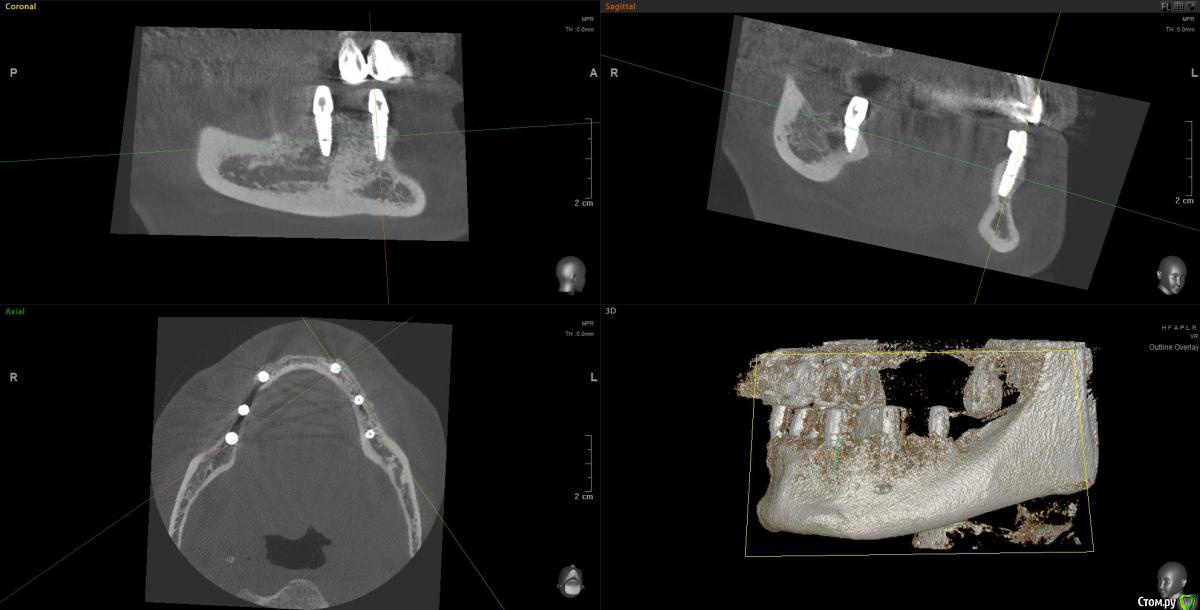

Kostoprav Опубликовано 14 июня, 2019 Поделиться Опубликовано 14 июня, 2019 Ксено+ауто +i prf, поверх титановых мембран перикард. кт через 5 мес.при и создании прикрепленки использовалась свиная дерма отечественного производителя 4 Ссылка на комментарий

L.E.S.I.K. Опубликовано 21 июня, 2019 Поделиться Опубликовано 21 июня, 2019 Миш не рекомендует объединять 4 импланта на полностью беззубой челюсти- если 2 установлены кпереди от ментальных отверстий и по одному дистально от ментальных на каждой стороне, мотивирую это скручиванием челюсти во время функции. 1 Ссылка на комментарий

Bier Опубликовано 28 июня, 2019 Поделиться Опубликовано 28 июня, 2019 Вы что на доктора напали? Нижняя челюсть изгибается во время открывания и закрывания рта, и процесса жевания. и действительно ряд авторов не рекомендует соединять имплантаты стоящие по разные стороны от ментального отверстия.И большое количество авторов вообще при протезировании полных дуг н.челюсти не устанавливают имплантаты дистальнее ментальных отверстий.Тем не менее и объединенные конструкции существуют. С большими сроками наблюдений их показывал Арам Давидян. 1 Ссылка на комментарий